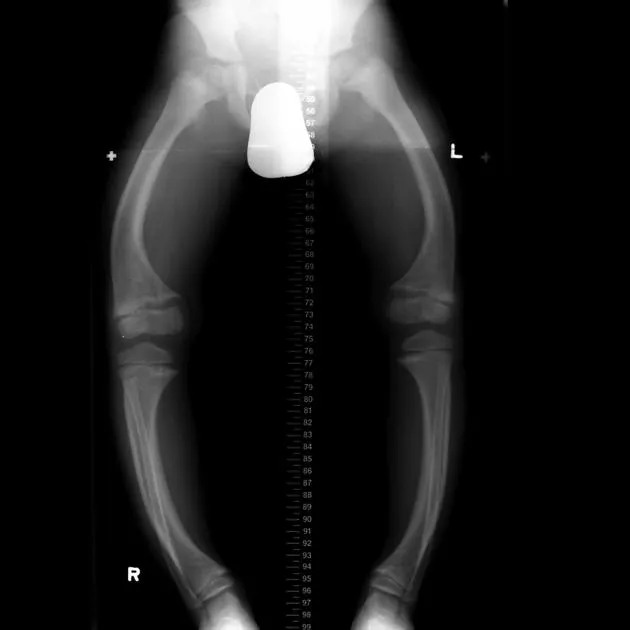

- Children (Rickets): Genu varum (bow-legs), rachitic rosary, craniotabes (soft skull).

⭐ High-Yield: Look for Looser zones (pseudofractures) on X-ray-transverse, lucent bands perpendicular to the cortex, classically in the femoral neck, scapula, or pubic rami.